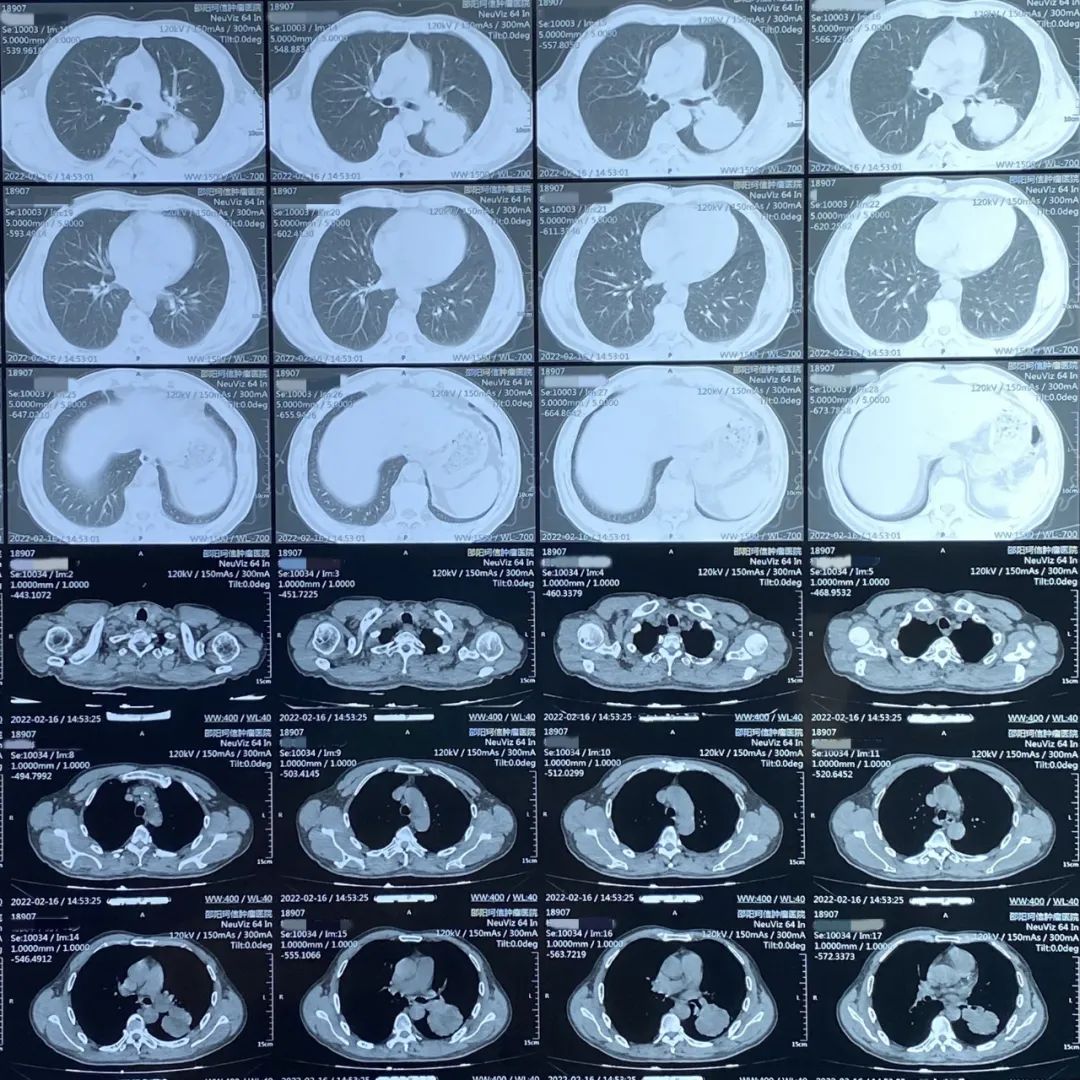

患者:男性,61歲,肺部腫瘤

患者因經常出現咳嗽、胸悶、氣喘等癥狀入院檢查,經CT檢查所示左肺有占位,病理活檢確診為肺部腫瘤。

肺部CT診斷